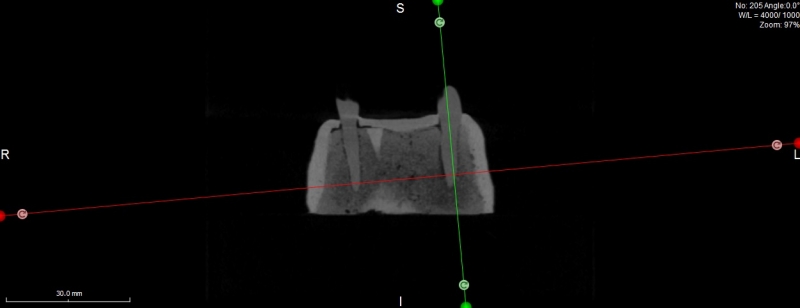

Żuchwa do fantomów z wyrostkiem zębodołowym wyścielonym imitacją błony śluzowej oraz zębami 10-3040

• Żuchwa do fantomów z wyrostkiem zębodołowym wyścielonym imitacją błony śluzowej oraz zębami 10-3040

Żuchwa do fantomów z wyrostkiem zębodołowym wyścielonym imitacją błony śluzowej oraz zębami wraz z ich korzeniami  w pozycji 37, 33, 43 oraz z niezagojonym zębodołem w pozycji 42. W modelu odwzorowano kanały żuchwy i otwory bródkowe. Płytka mocująca umożliwia montaż do większości fantomów znajdujących się na rynku. Model ten można zamontować w dowolnym artykulatorze lub fantomie dentystycznym popularnym na rynku (zalecany manekin to 11-1000).

Poniżej znajduje się przycisk umożliwiający ściągnięcie pliku STL przeznaczonego do wykonanie szablonu do szkoleń implantacyjnych z użyciem modelu.

Numer katalogowy 10-3040